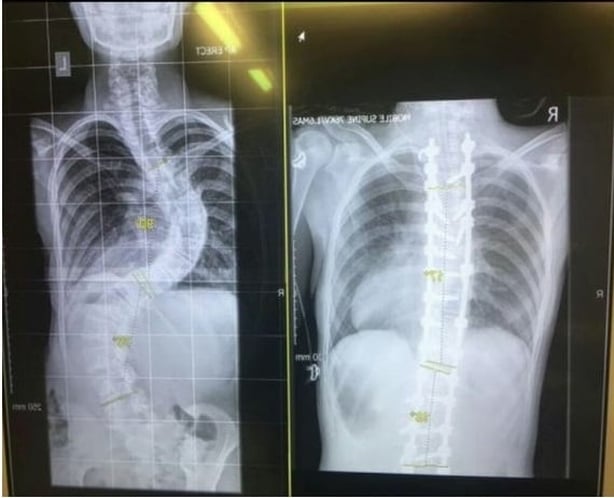

These "Before" and "After" x-rays illustrate the impact of the surgery.

Following Megan's operation in Crumlin Children's Hospital yesterday her spine is now almost completely straight.